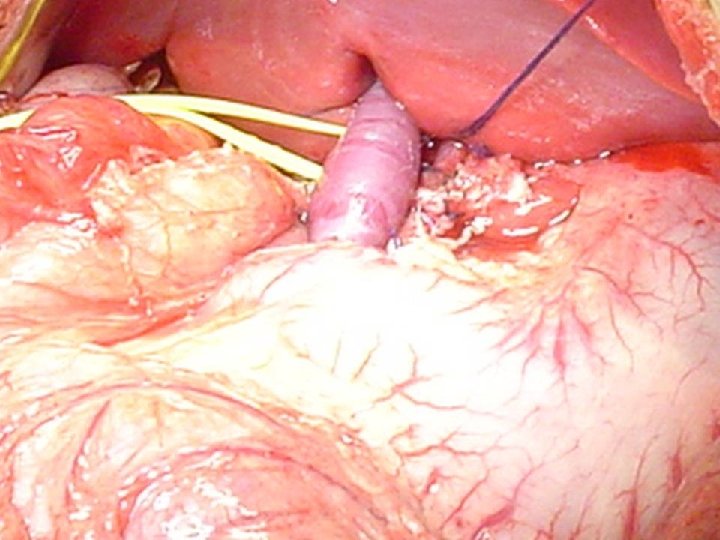

CONCEITO DO REX SHUNT MESO-LEFT PORTAL BY PASS 1 - LOCALIZAÇÃO PELO LIGAMENTO REDONDO DO FÍGADO DO RAMO ESQUERDO DA VEIA PORTA- INTRA HEPÁTICA 2 - DETERMINAR PATENCIA DO FLUXO PORTAL INTRAHEPÁTICO 3 - REALIZAR SHUNT MESENTÉRICO –PORTA ESQUERDA – JUGULAR- ILÍACA

Casuística pessoal – 12 casos n n Menino 9 anos – TVP Inúmeras internações por sangramento digestivo- 23 escleroterapias de varizes. Esplenectomia aos 3 anos Rex Shunt com jugular interna n Follow up- 5 anos - Sem complicações sem varizes esofágicas Otimo desempenho escolar n

Casuística pessoal – 12 casos n Menina 7 anos -TVP- inúmeras internações por sangramento digestivo- 32 escleroterapia de varizes. n Rex Shunt com jugular interna Trombose de Shunt com 6 mêses Novo Rex, com Ilíaca Interna Follow up- 4 anos Sem sangramento – Baço sp. Sem Varizes esofágicas Otima aprendizagem escolar. n n n